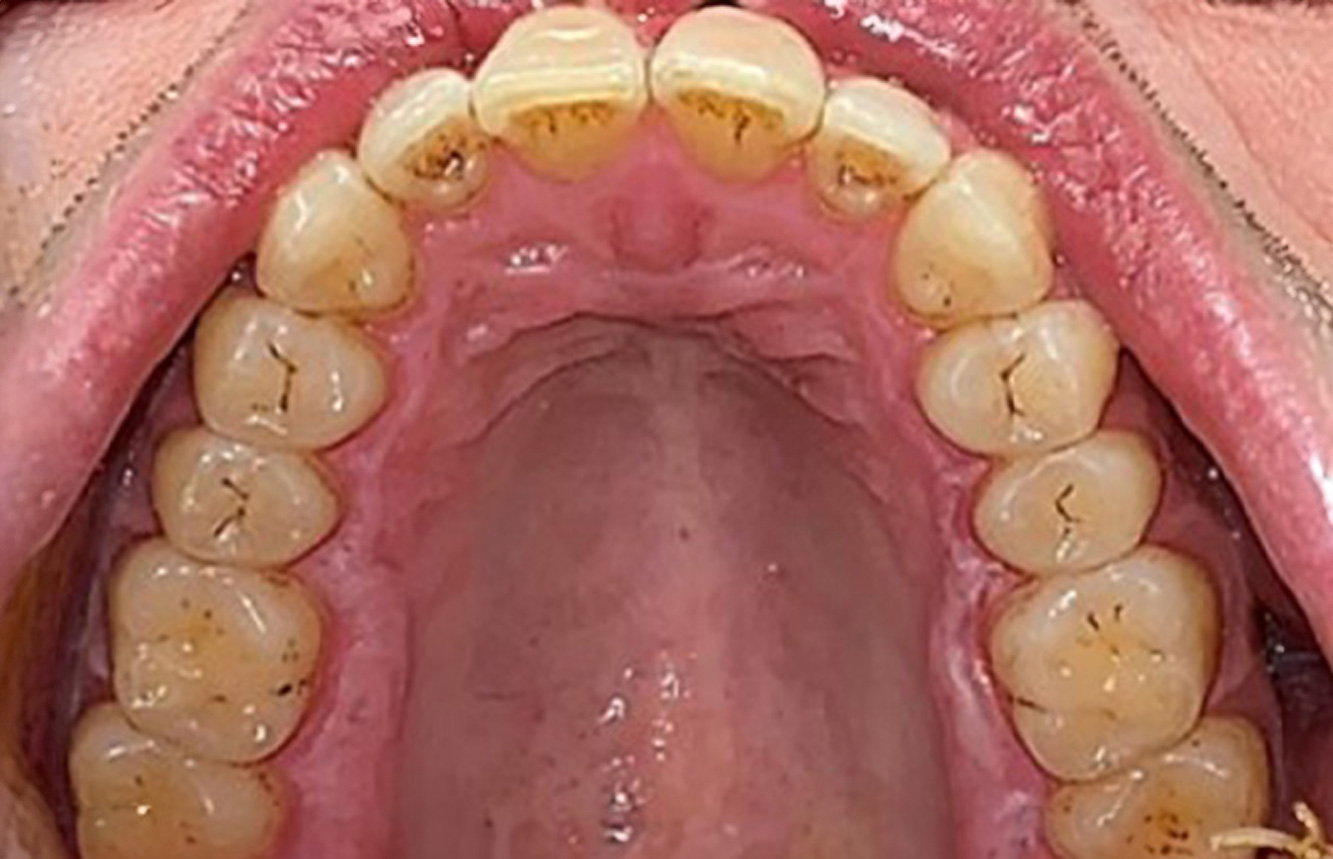

The healthy patient with pre-existing periodontal disease & peri-implantitis

A 52-year-old patient presents at a preventive care session. The patient has no systemic disease and is not taking any medication. He has had various dental treatments and also has two active carious lesions. In addition, the patient has four implants (2nd, 3rd and 4th quadrants). He is revealed to have early periodontal disease (stage IV, grade B). His periodontal condition is stable; a probing depth of Probing depths (ST) of 5 mm is only evident at the implant in region 36. Gingivitis is also identified. more